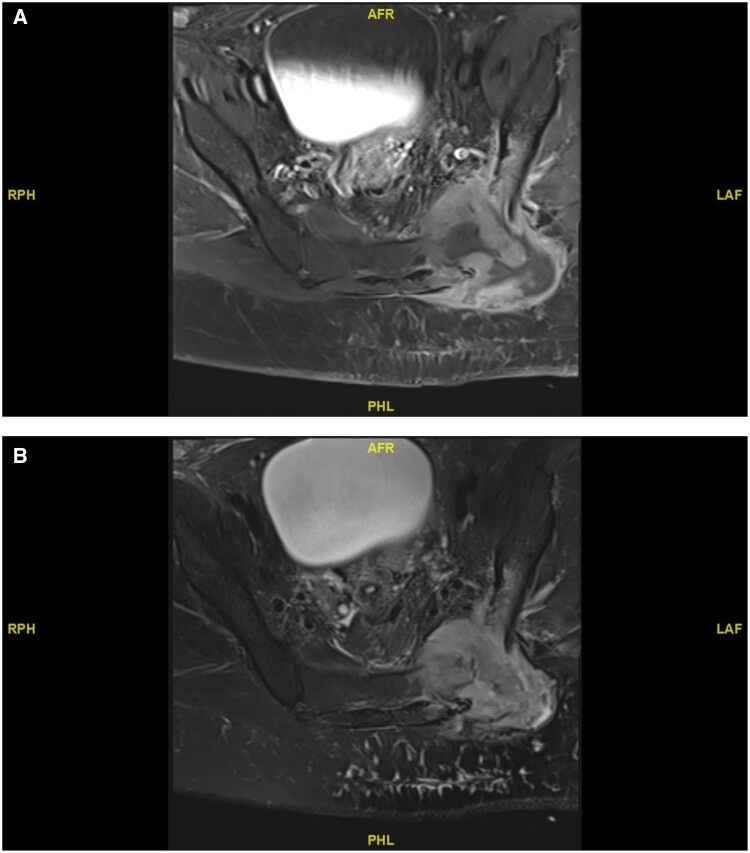

Classic Hodgkin lymphoma is a potentially curable disease. With the advent of effective systemic regimens with adriamycin, bleomycin, vincristine, and dacarbazine, chemotherapy has become the treatment of choice for advanced Hodgkin lymphoma. However, for advanced Hodgkin lymphoma after chemotherapy, disease relapse rates are still high. This case report highlights how low-dose palliative radiotherapy can be used successfully for the management of an unusual case of recurrent lymphoma with a different histology soon after completing systemic therapy, which was further complicated by an ongoing local infection.